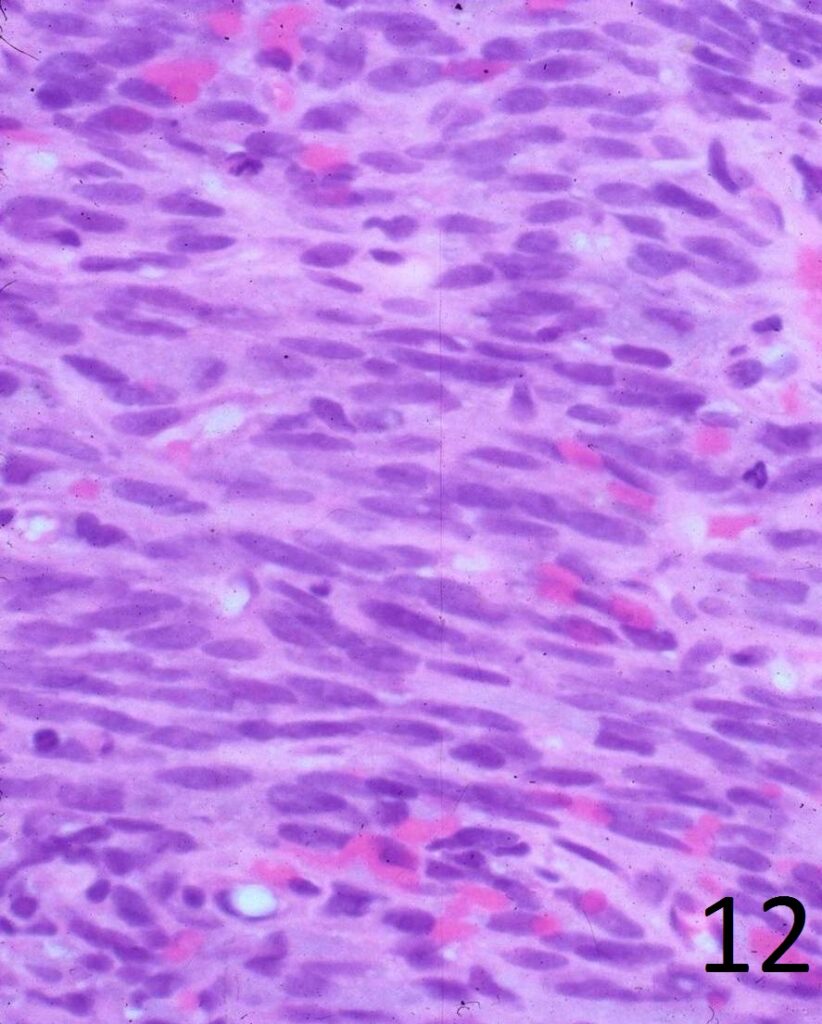

Microscopic

• Elongated, fairly uniform spindle cells with scant cytoplasm in a fibrous stroma

• Large nuclei with abnormal mitoses present; Higher grade tumors have more mitoses, necrosis and pleomorphism.

• Minimal pleomorphism with low grade tumors; More pleomorphism and mitoses with higher grade tumors

• Nuclei appear elongated with round ends (Fig. 12)